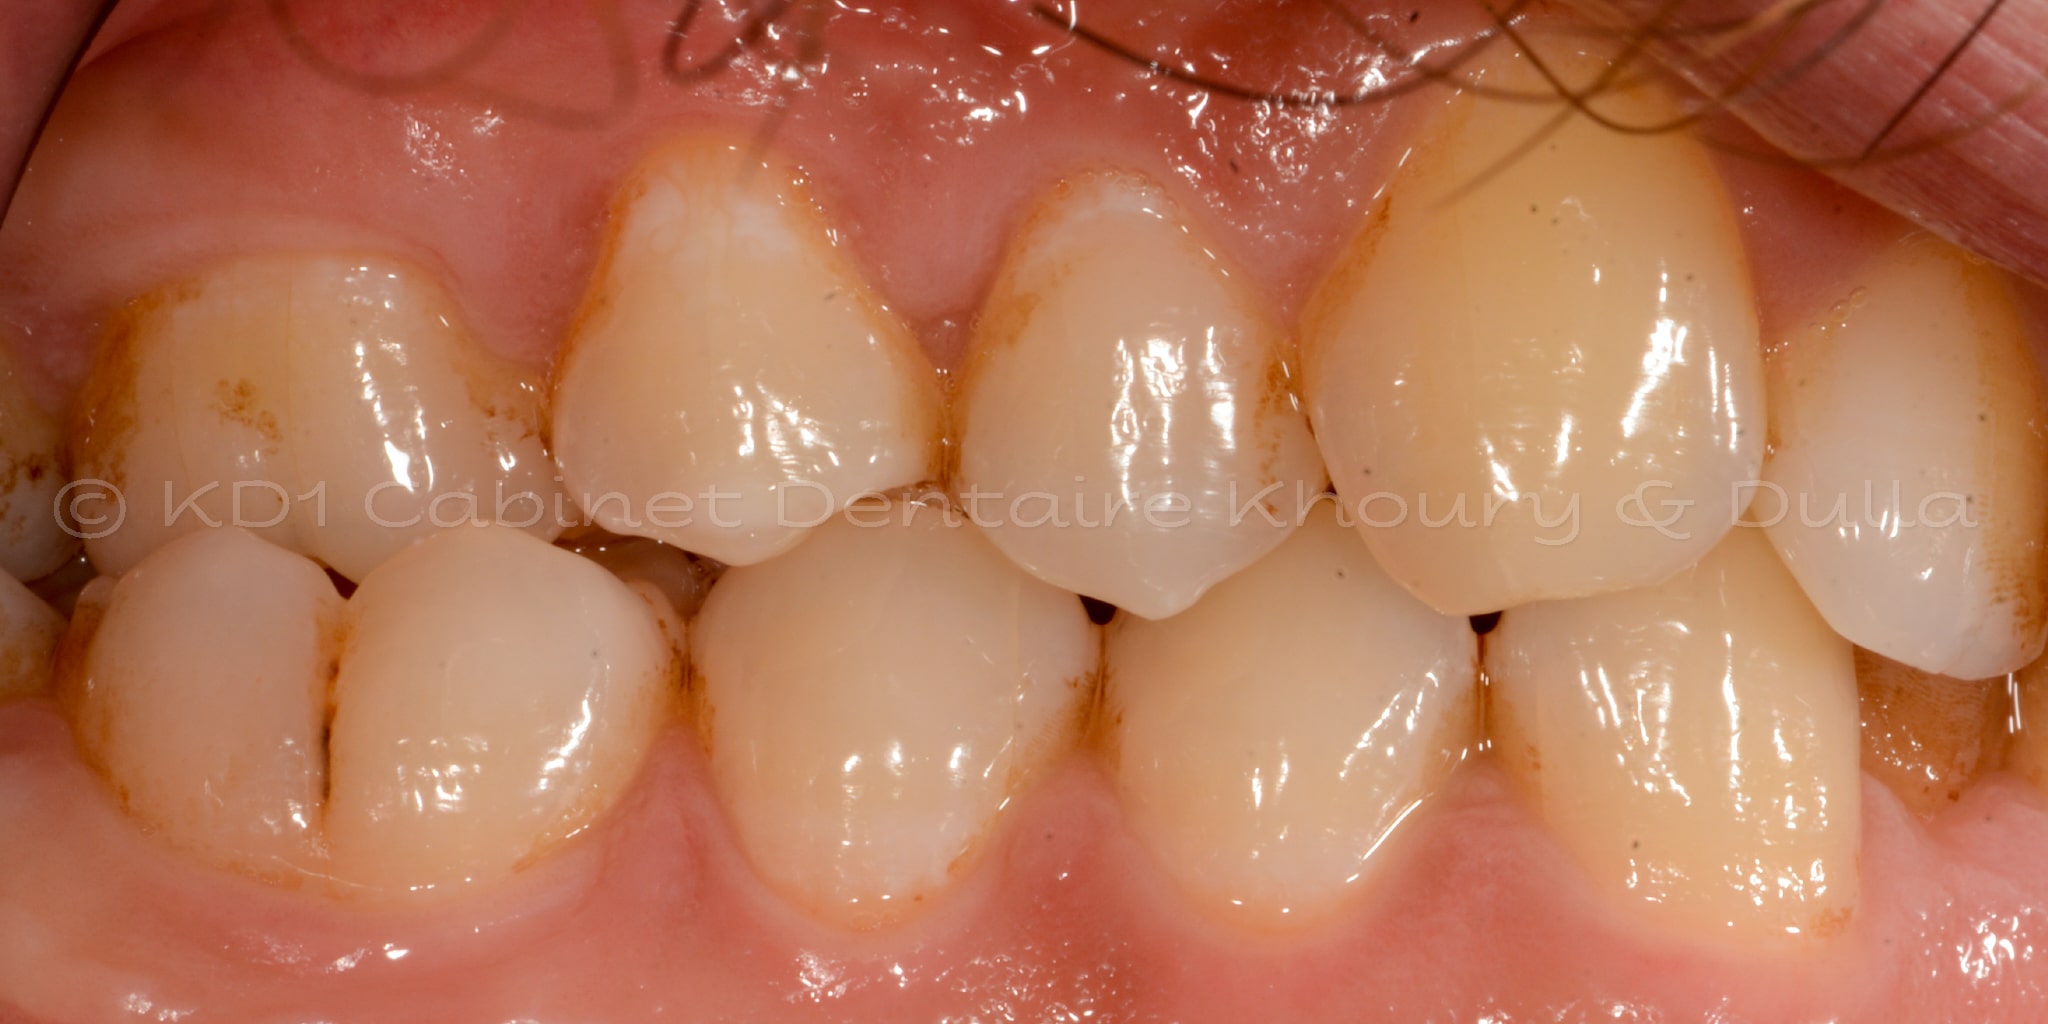

Cas #1 – Traitement avec des bagues, deuxièmes prémolaires et dent de sagesse supérieures ectopiques.